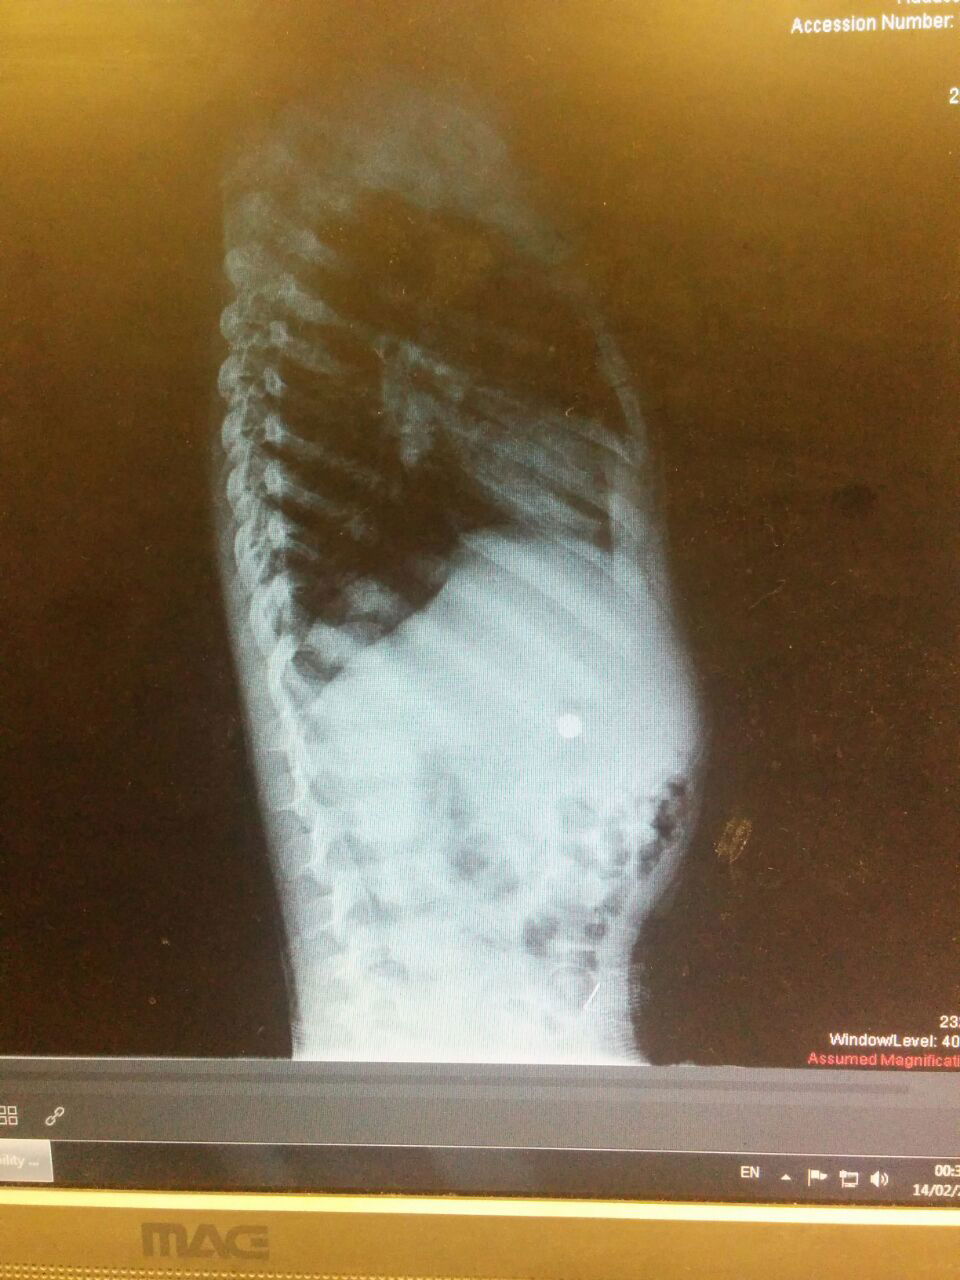

המקרה השלישי לא אחר לבוא. עוד באותה משמרת הגיע ילד בן ארבע למיון, אשר בלע סוללת כפתור. המידות הקטנות של הסוללה, בסיוע החלקלקות של העצם הזר הזה - שיחקו לטובת הילד והסוללה התקדמה לכיוון היציאה הטבעית מקיבתו של הילד, זאת תחת מעקב הצוות אשר חשש מהרעלה מסוכנת אשר יכולה להיגרם כתוצאה מבליעתה.